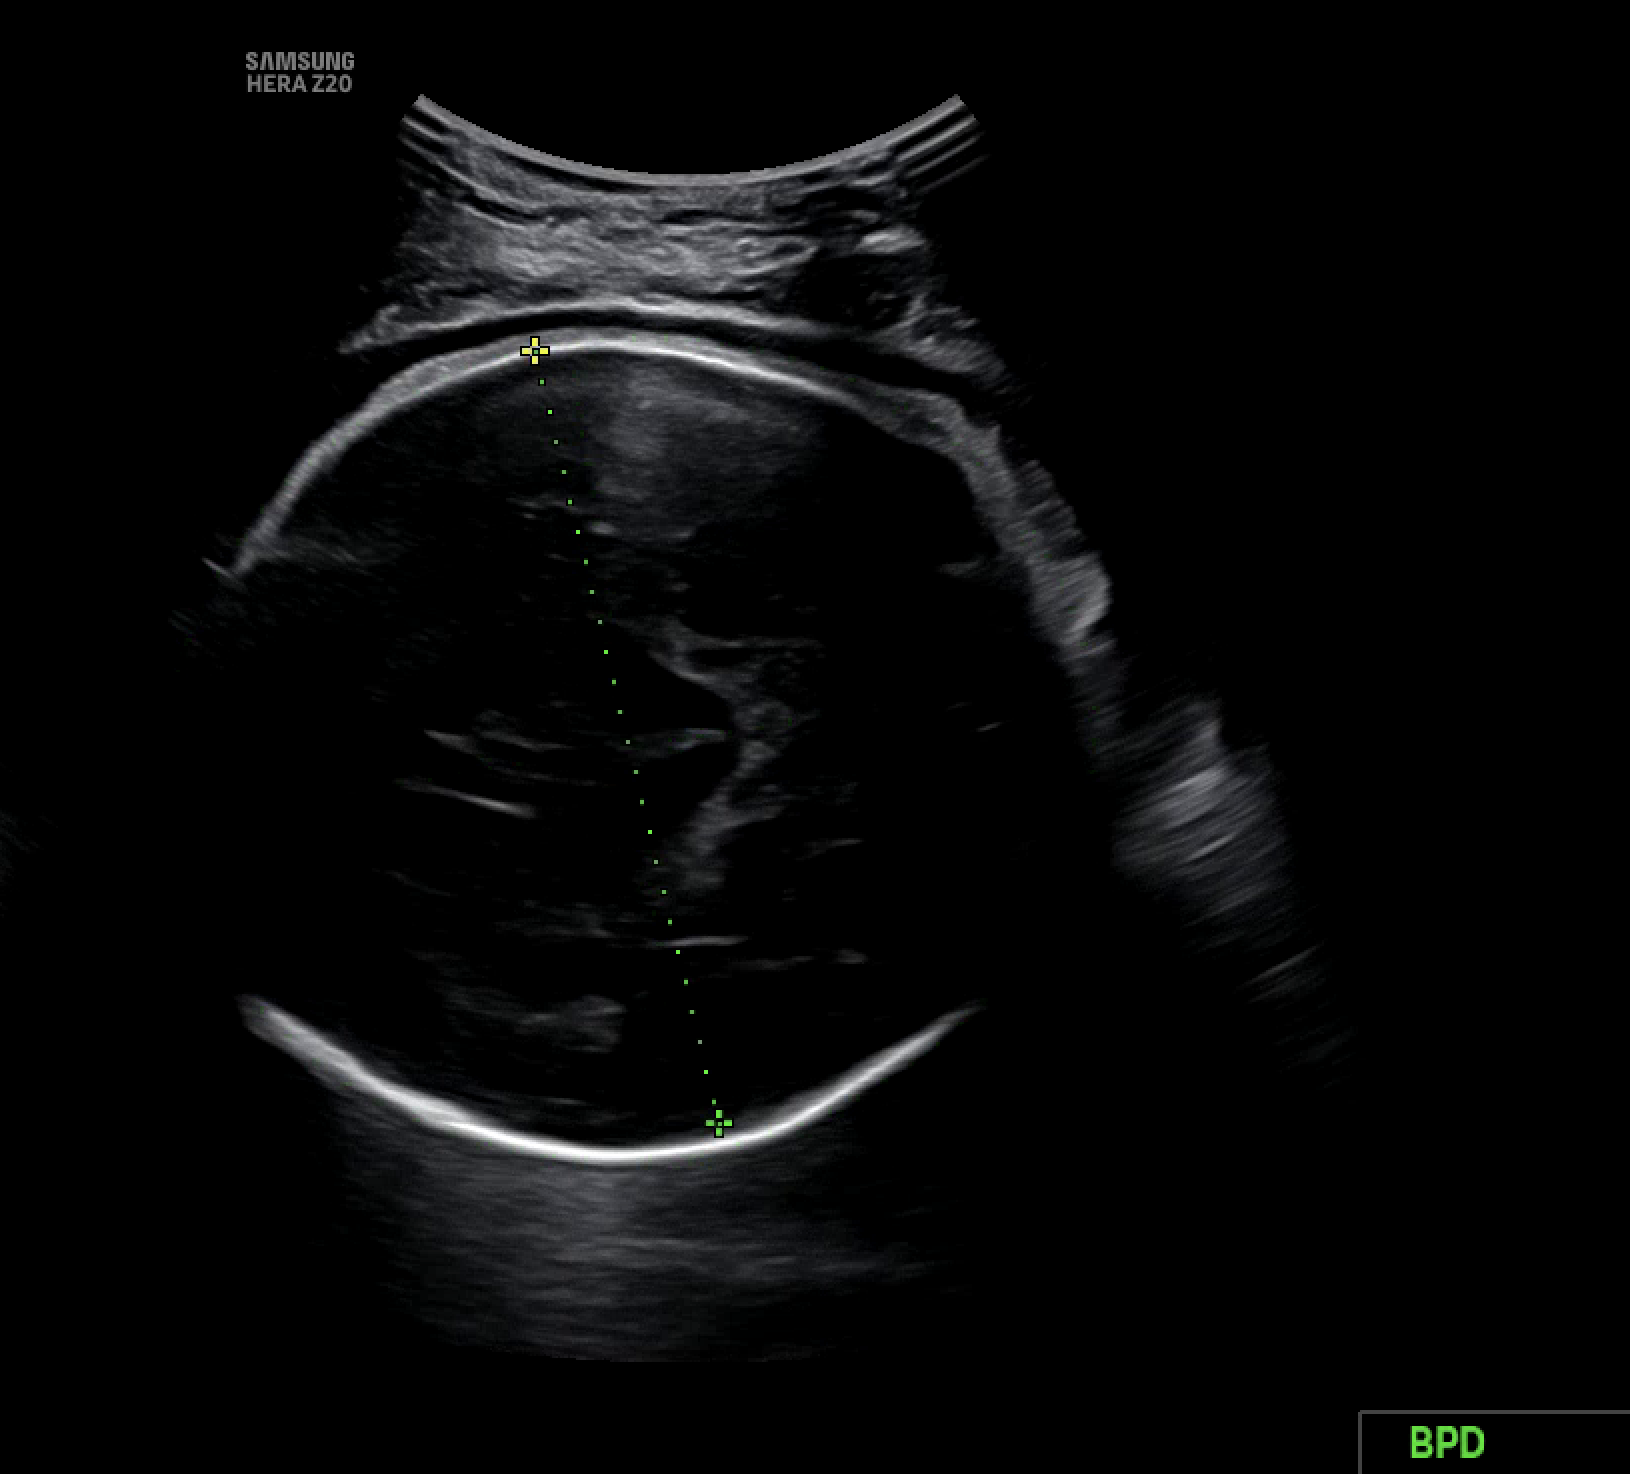

초기에는 초음파 영상이 입체인지 아닌지를 구분하는 것이 핵심 과제였다. 하지만 새로운 서비스 준비와 함께, 이미지 분류 기준을 보다 정교하게 세분화할 필요성이 생겼고, 이는 애초에 내가 지향했던 방향이기도 하다. 단순히 입체 여부를 판단하는 것을 넘어, 영상에 어떤 성장 지표가 (예: AC, BPD, FL) 포함되어 있는지를 구체적으로 분류하고 싶었다. 수많은 시행착오 끝에 구조가 또렷이 보이는 이미지는 ac, bpd, fl 등 긍정 클래스로, 구조 식별이 어려운 이미지는 부정 클래스로 나눠 학습시켰다.

여기서 핵심 기준은 영상 내 십자가 모양의 마커와 (marker) 어노테이션의 (annotation) 존재 여부다.

- 마커와 어노테이션 모두 있는 경우 → 긍정 클래스로 분류 (ac, bpd, fl 등)

- 마커는 없지만 어노테이션이 있는 경우 → no_xxx 클래스로 분류

- 마커도 없고 어노테이션도 없는 경우 → na_xxx 클래스로 분류